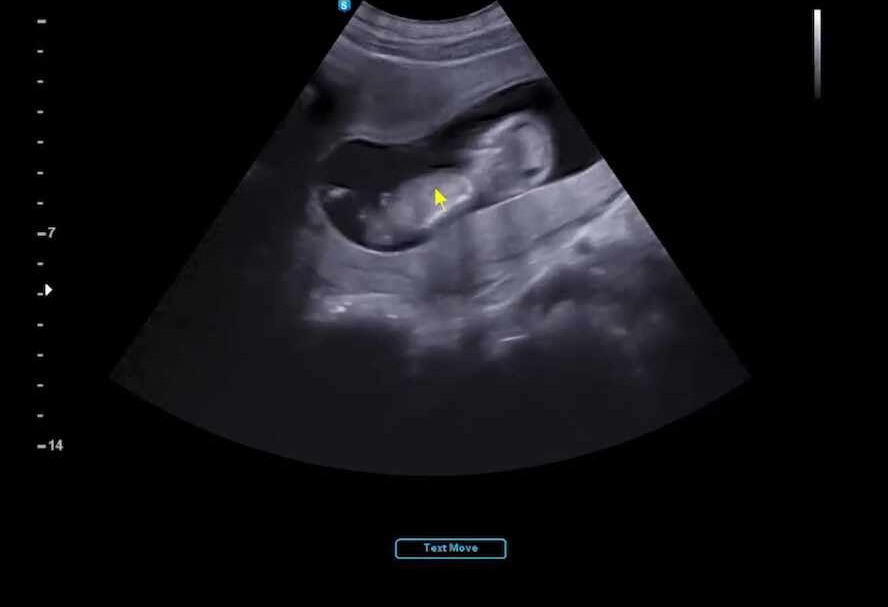

12주가 되어서는 1차 기형아 검사 및 정밀 초음파를 보러 갔다.

은근히 긴장이 되었는데 다행히 우리 튼튼이는 목투명대가 0.84mm로 안전하게 통과했다.

(보통 3mm 이상이면 정밀 검사가 필요하다)

9주에 초음파를 보고 3주 만에 초음파를 봤는데 6센티가 조금 넘는 아이가 인간의 형태를 띠고 있어서 정말 깜짝 놀랐다.

무엇보다 이 조그만 6센티짜리 귀요미 미니미가 배안에서 막 뛰어노는데 정말 정말 귀엽고 내 안에 사람이 있다는 사실이 다시 한번 실감 나기 시작했다.